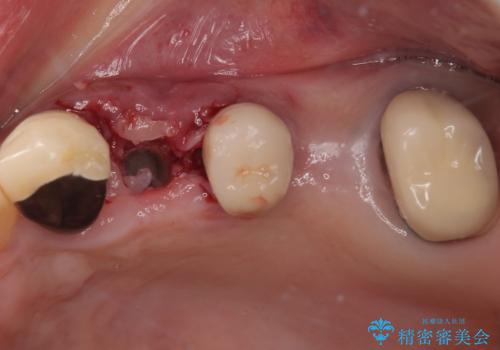

プラスチックを外すと同時に抜歯を行い、1ヶ月ほど待機して歯肉が落ち着いたことを確認してから速やかにインプラントを埋入することとしました。

従来は4ヶ月ほど待機してからの埋入が一般的でしたが、歯肉の炎症が落ち着いた時点で速やかに埋入できるようになり、4ヶ月の短期間で治療を終えることができました。